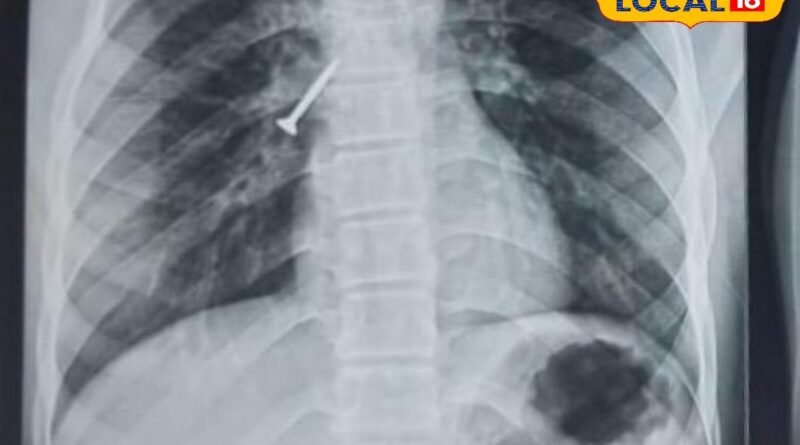

Udaipur News: उदयपुर में मेडिकल चमत्कार! बिना ऑपरेशन और बिना बेहोशी सांस की नली से निकाला 32MM का स्क्रू

Udaipur Doctors Medical Miracle: उदयपुर के डॉक्टरों ने एक अनोखा और चुनौतीपूर्ण केस सफलतापूर्वक संभालते हुए बिना ऑपरेशन और बिना बेहोशी के मरीज की सांस की नली से 32MM का स्क्रू निकाल दिया. यह प्रक्रिया ब्रोंकोस्कोपी तकनीक के जरिए की गई, जिसमें बिना चीरा लगाए अंदर फंसी वस्तु को सुरक्षित बाहर निकाला जाता है. इस दौरान डॉक्टरों ने अत्यंत सावधानी और कौशल का परिचय दिया, जिससे मरीज को किसी प्रकार की जटिलता का सामना नहीं करना पड़ा. यह सफलता आधुनिक चिकित्सा तकनीक और विशेषज्ञता का बेहतरीन उदाहरण है, जो भविष्य में ऐसे मामलों के लिए नई उम्मीद जगाती है.